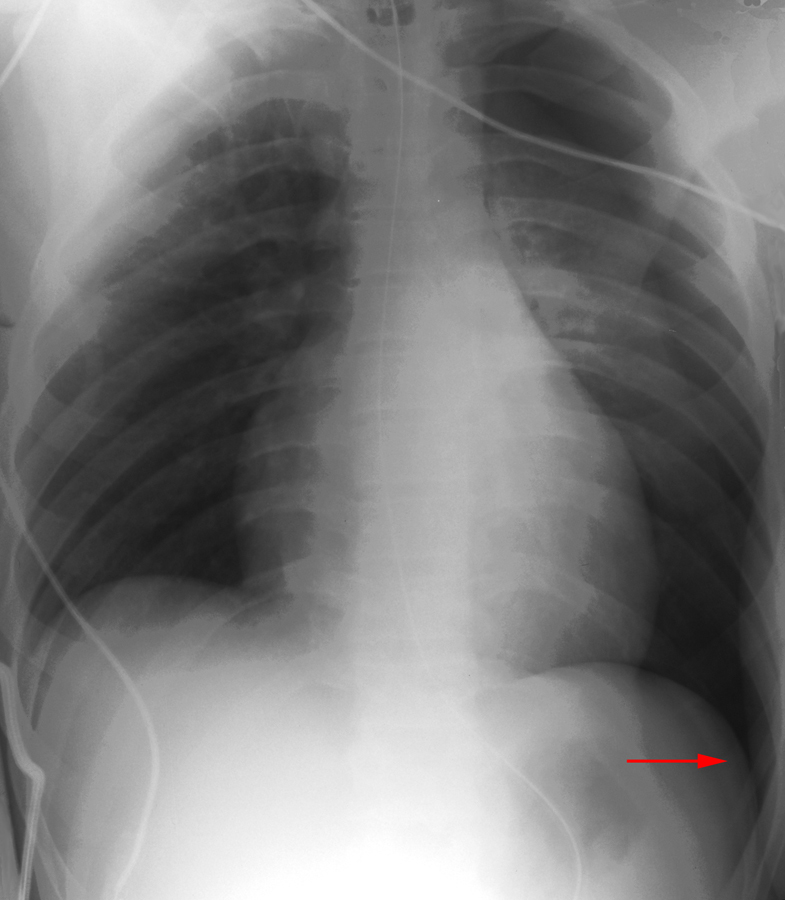

Pneumothorax in the Supine Patient

In the supine patient, intrapleural air rises anteriorly and medially, often making the diagnosis of pneumothorax difficult. The anteromedial and subpulmonary locations are the initial areas of air collection in the supine patient. An apical pneumothorax in a supine patient is a sign that a large volume of air is present. Subpulmonic pneumothorax occurs when air accumulates between the base of the lung and the diaphragm. Anterolateral air may increase the radiolucency at the costophrenic sulcus. This is called the deep sulcus sign. Other signs of subpulmonic pneumothorax include a hyperlucent upper quadrant with visualization of the superior surface of the diaphragm and visualization of the inferior vena cava.

Subpulmonary Pneumothorax

Occasionally, a posterior subpulmonary pneumothorax will result in visualization of the more superior anterior diaphragmatic surface and the inferior posterior diaphragmatic surface, resulting in the double-diaphragm sign.